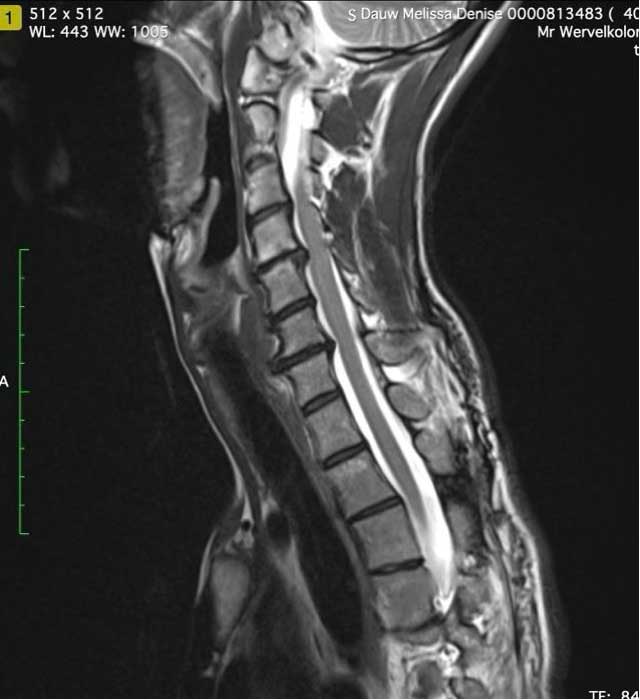

Ce spécialiste parle de spondylose dans le cou.

Lorsque les vertèbres cervicales supérieures bougent trop (sont instables), le corps essaie de compenser en rendant les vertèbres cervicales inférieures plus rigides.

Avec le temps, cette surutilisation entraîne une spondylose (usure) du reste du cou ( ).

En outre, l’angio-IRM montre que les veines jugulaires sont comprimées, ce qui est également progressif sans intervention chirurgicale et provoque une « surpression du liquide céphalo-rachidien », ce qui signifie une pression cérébrale élevée.